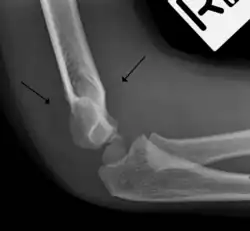

Fat pad sign

The fat pad sign, also known as the sail sign, is a potential finding on elbow radiography which suggests a fracture of one or more bones at the elbow. It may indicate an occult fracture that is not directly visible. Its name derives from the fact that it has the shape of a spinnaker (sail).[1] It is caused by displacement of the fat pad around the elbow joint. Both anterior and posterior fat pad signs exist, and both can be found on the same X-ray.

In children, a posterior fat pad sign suggests a condylar fracture of the humerus. In adults it suggests a radial head fracture.

The fat pad sign is invaluable in assessing for the presence of an intra-articular fracture of the elbow. An anterior fat pad is often normal. However a posterior fat pad seen on a lateral x-ray of the elbow is always abnormal. The patient will be unable to flex their elbow and requires orthopaedic input.[2]

The posterior fat pad is normally pressed in the olecranon fossa by the triceps tendon, and hence invisible on lateral radiograph of the elbow.[3] When there is a fracture of the distal humerus, or other pathology involving the elbow joint, inflammation develops around the synovial membrane forcing the fat pad out of its normal physiologic resting place. This is visible as the "posterior fat pad sign" and is often the only visible marker of a fracture, particularly in the pediatrics population.